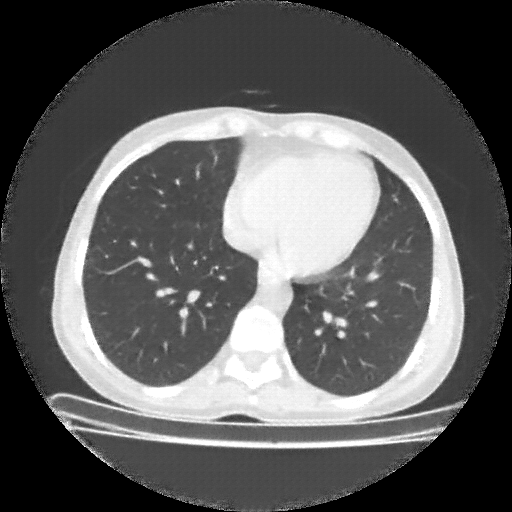

Original NATIVE CT scan (input)

Full window (WL 1023.5, WW 4095 β†’ Low βˆ’1024, High +3071)

Actual HU range: [-1024.0, 1173.0]

Lung window (WL -600, WW 1500 β†’ Low βˆ’1350, High +150)

Actual HU range: [-1350.0, 150.0]